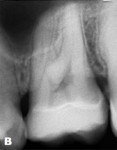

The clinical case involved a preparation of a vital tooth No. 26 with a substantially damaged occlusal surface from erosion (Figure 1 and Figure 2). The patient was a 27-year-old man, who frequently drank sparkling sweet drinks and had good oral hygiene. Demineralization of the enamel provided loss of hard tissues (index score = 3), and a conservative approach was taken.

Insertion of the Restoration

A pressed12 or milled (CAD/CAM)13 glass-ceramic restoration was bonded using dual-cure adhesive resin cement (Figure 12 and Figure 13). In this case, Vitablocs® Mark II ceramic (Vita Zahnfabrik, vita-zahnfabrik.com) and RelyX™ Ultimate (3M ESPE, 3m.com) were used.